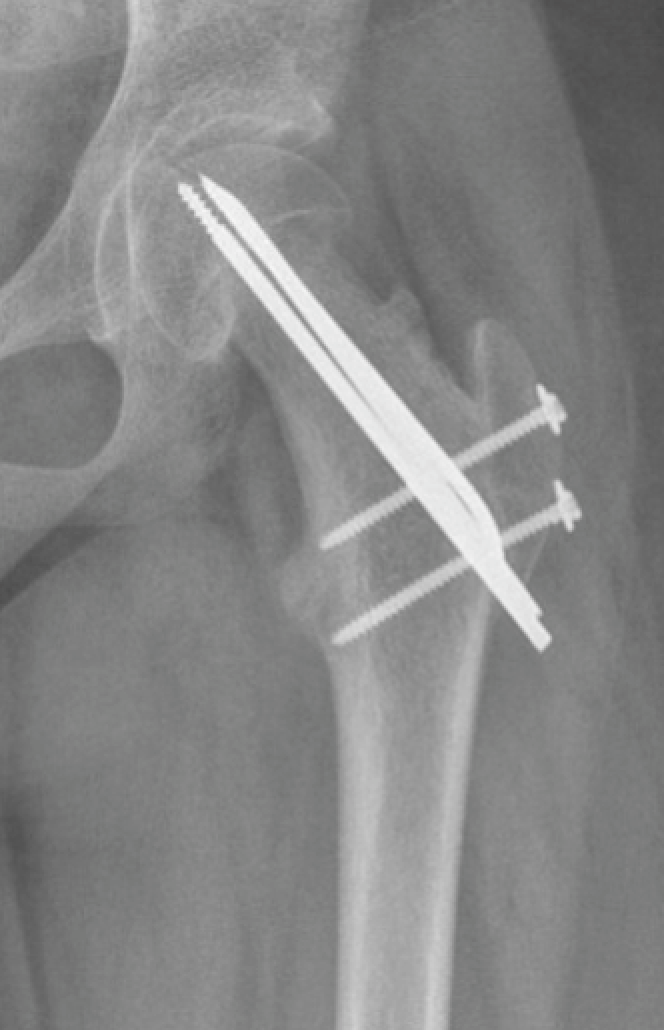

Als de verplaatsing toch groot is dan zal de heupkop chirurgisch terug op de goede plaats gezet worden en eveneens gefixeerd worden met 3 pinnen. De ingreep gebeurt via een surgical dislocation.